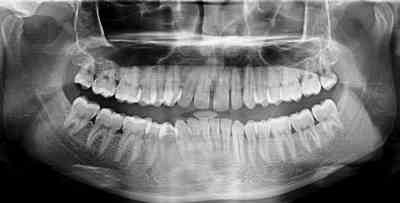

Case 2: A 22-year male patient reported to the department of dentistry after a road traffic accident. There was swelling in the left preauricular region with a history of ear bleed. Painful movements of the mandible were observed without any restrictions in mouth opening. Condyle was present in the glenoid fossa, and movements were perceptible bilaterally. The O.P.G revealed no fracture in either condyle, but the C.T. showed a sagittal fracture of the left condylar head and a medial displacement of the medial fragment. A soft diet and limited mouth opening were advised for two weeks.

Figure 5. Case 2: Conventional radiograph (OPG).